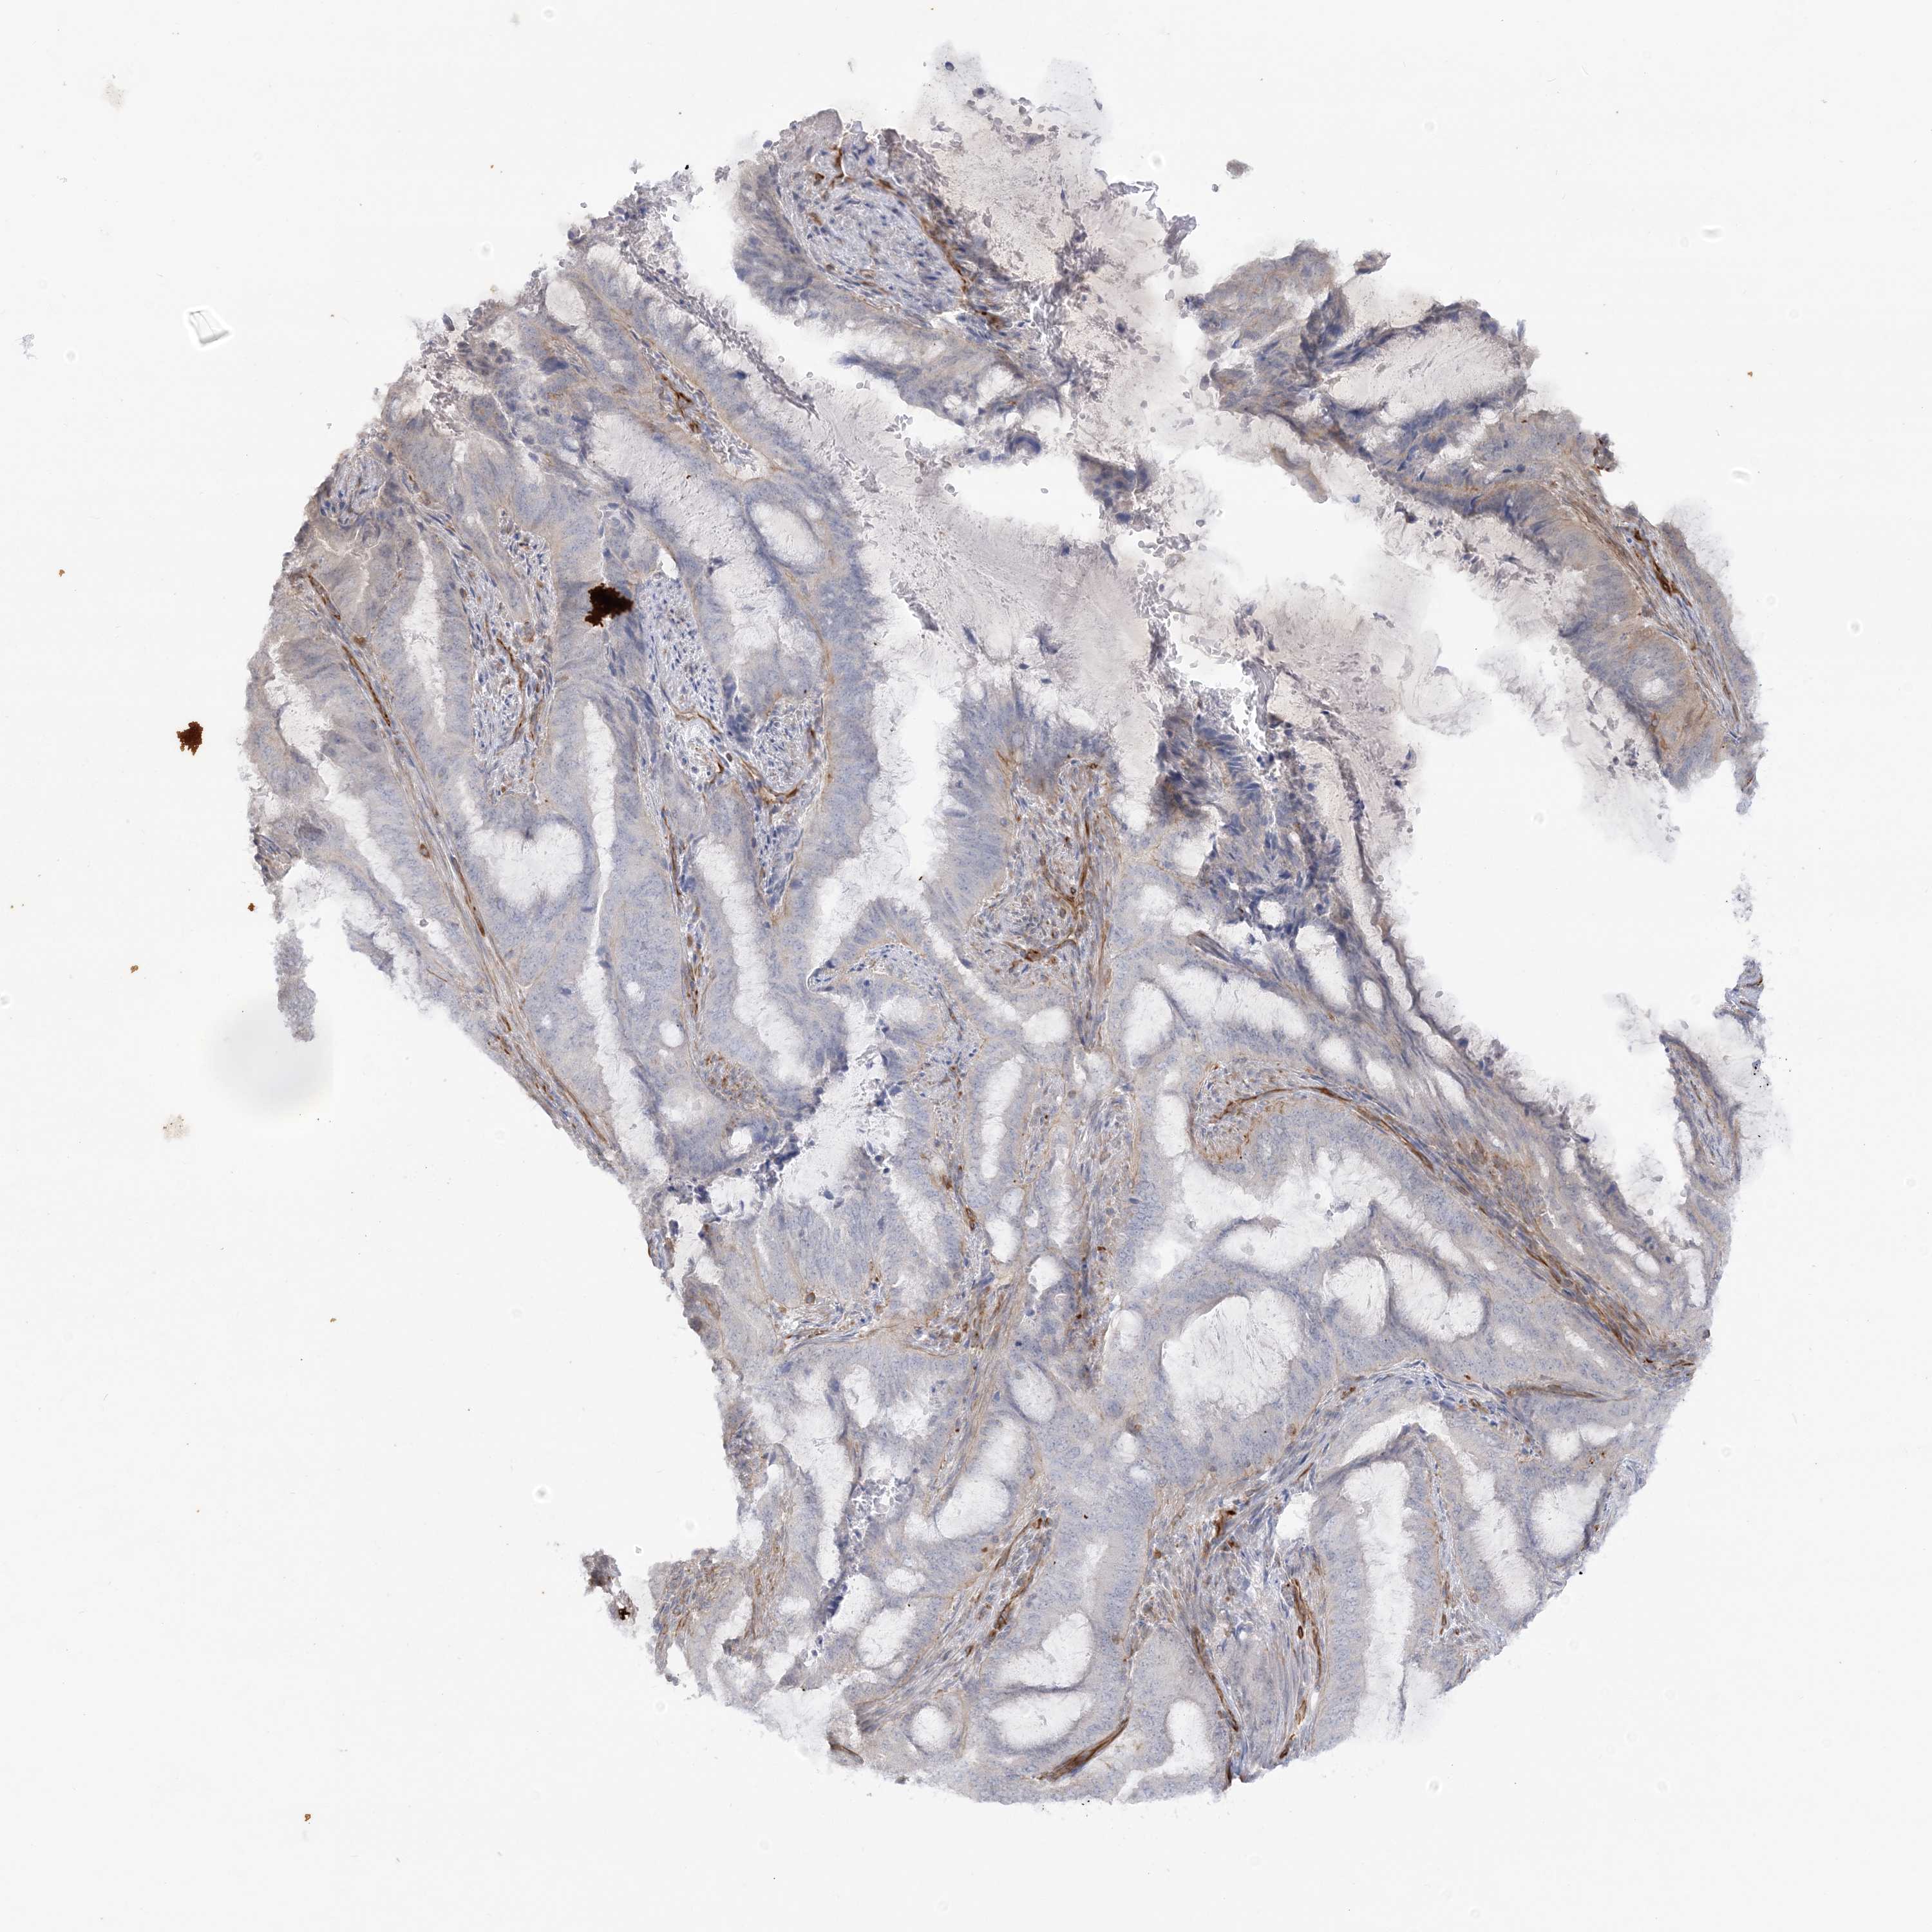

ENDOMETRIAL CANCER - Protein expressioni

A mouse-over function shows sample information and annotation data. Click on an image to view it in a full screen mode. Samples can be filtered based on level of antibody staining by selecting one or several of the following categories: high, medium, low and not detected. The assay and annotation is described here.

Note that samples used for immunohistochemistry by the Human Protein Atlas do not correspond to samples in the TCGA dataset.

Antibody stainingi

Antibody staining in the annotated cell types in the current human tissue is reported as not detected, low, medium, or high, based on conventional immunohistochemistry profiling in selected tissues. This score is based on the combination of the staining intensity and fraction of stained cells.

Each image is clickable and will lead to virtual microscopy that enables deeper exploration of all samples and also displays staining intensity scores, fraction scores and subcellular localization as well as patient and tissue information for each sample.

Antibody HPA036560

Antibody HPA036561

Staining

High

Medium

Low

Not detected

Intensity

Strong

Moderate

Weak

Negative

Quantity

>75%

75%-25%

<25%

None

Location

Nuclear

Cytoplasmic/membranous

Cytoplasmic/membranous,nuclear

Adenocarcinoma, NOS